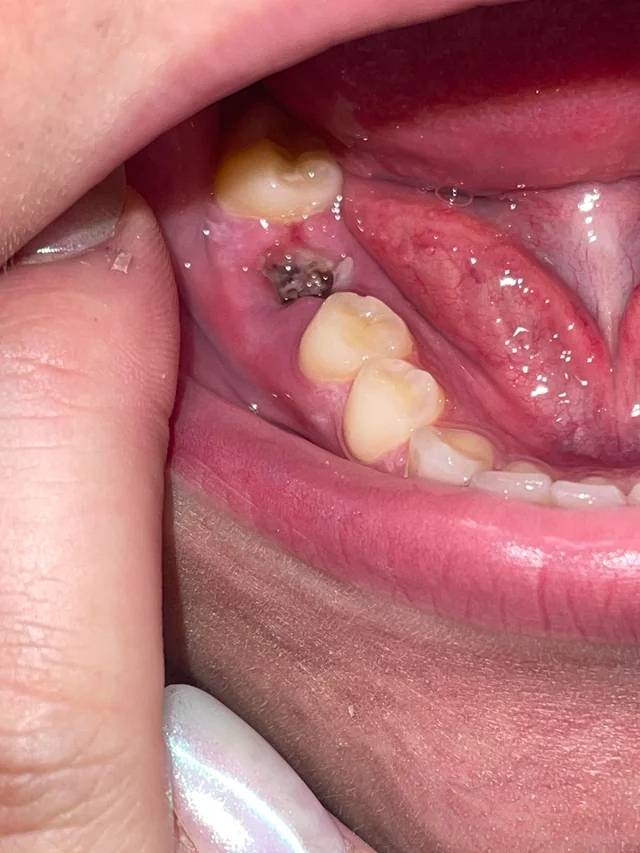

Quick visual impression (from the photo)

The socket shows a dark area in the extraction site — that can be a blood clot or residual blood/debris.

I don’t clearly see obvious pus or gross swelling in this photograph, but the image is limited (lighting, angle, saliva and soft-tissue can hide signs).

Because the extraction was just yesterday, it is very early to tell: normal early healing often looks like a dark/blackish clot in the first 24–48 hours.

From the photo alone (extraction yesterday) it most likely looks like a normal early clot — too soon to declare dry socket or infection.